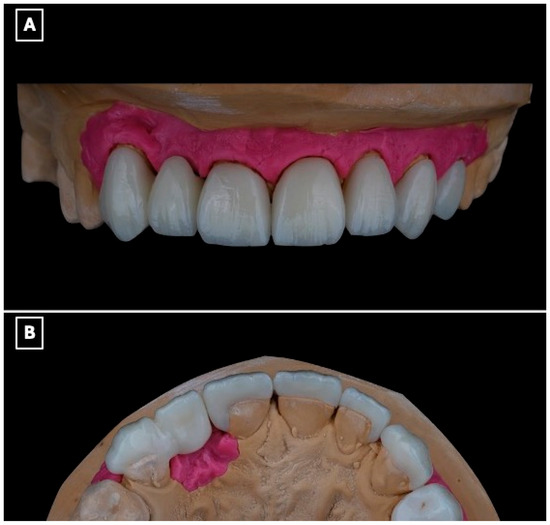

The definitive restoration was fabricated as a full-contour lithium disilicate prosthesis using a low-translucency ingot (IPS e.max Press, Ivoclar Vivadent, Schaan, Liechtenstein). The prosthesis incorporated a single-retainer cantilever design with a modified ridge-lap pontic to optimize esthetics, biomechanics, and hygiene (Figure 4A,B). The single-retainer configuration was deliberately selected to eliminate differential abutment mobility and reduce interfacial shear stresses commonly associated with fixed-fixed designs. The palatal retainer was confined entirely to enamel and designed with smooth, well-defined margins to maximize adhesive bonding while preserving sound tooth structure (Figure 4B). Connector dimensions were carefully controlled to provide adequate fracture resistance without over-contouring, balancing mechanical strength with esthetic requirements. A modified ridge-lap pontic design was employed to achieve a natural emergence profile while maintaining a cleansable contour, allowing passive tissue contact and facilitating effective oral hygiene (Figure 4A,B).

Figure 4.

Definitive lithium disilicate single-retainer cantilever resin-bonded fixed dental prosthesis illustrating key design features. (A) Labial view showing the esthetic integration of the restoration within the anterior smile zone and the single-retainer cantilever configuration, selected to eliminate differential abutment mobility and reduce interfacial shear stresses at the adhesive interface. (B) Palatal view illustrating the enamel-bonded palatal retainer with a defined connector region and a modified ridge-lap pontic design, providing controlled tissue contact for esthetics while facilitating oral hygiene access and minimizing plaque accumulation at the pontic-tissue interface.

The patient reported satisfaction with the esthetic and functional outcomes of the treatment. Follow-up evaluations at 1 week, 1 month, 6 months, 1 year, and 18 months showed maintained adhesive retention, healthy peri-abutment soft tissues, and no evidence of technical or biological complications during the observation period (Figure 8A–C).

Figure 8.

Intraoral views at the 18-month follow-up demonstrate clinical stability of the restoration. (A) Frontal intraoral view showing stable esthetic integration of the cantilever RBFDP and laminate veneers within the smile. (B) Close-up frontal view highlighting maintained color stability, intact adhesive margins, and healthy peri-gingival tissues, suggesting favorable short- to medium-term adhesive performance. (C) Lateral intraoral view illustrating functional integration and preservation of occlusal relationships, with no evidence of chipping, debonding, or excessive wear at the cantilever region.